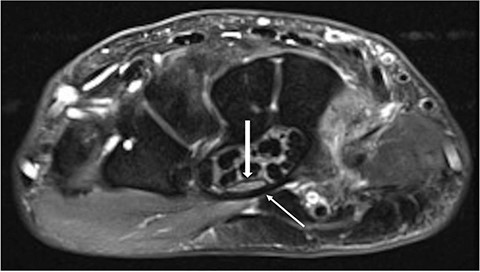

Clinically, the patient was initially diagnosed with a bilateral carpal tunnel syndrome confirmed by electromyogram (EMG)/nerve conduction velocity (NCV) (Fig. 1), which was treated surgically in the typical manner and led to freedom from symptoms. Over the further course, diffuse pain occurred in both legs, and the pain-free walking distance decreased over time. Colour coded duplex sonography (CCDS) did not reveal any evidence of peripheral arterial occlusive disease. Diabetes mellitus could be excluded by laboratory tests. In the imaging diagnostics carried out by means of magnetic resonance imaging (MRI) of the axial skeleton, an absolute spinal canal stenosis at the level of vertebral bodies L4–L5 due to a marked hypertrophy of the ligamenta flava with additional deforming spondylosis could be confirmed (Fig. 2).

Axial MRI slice showing the carpal tunnel. A thickened transverse carpal ligament (thin arrow) with a clear indentation of the median nerve (thick arrow) is shown.